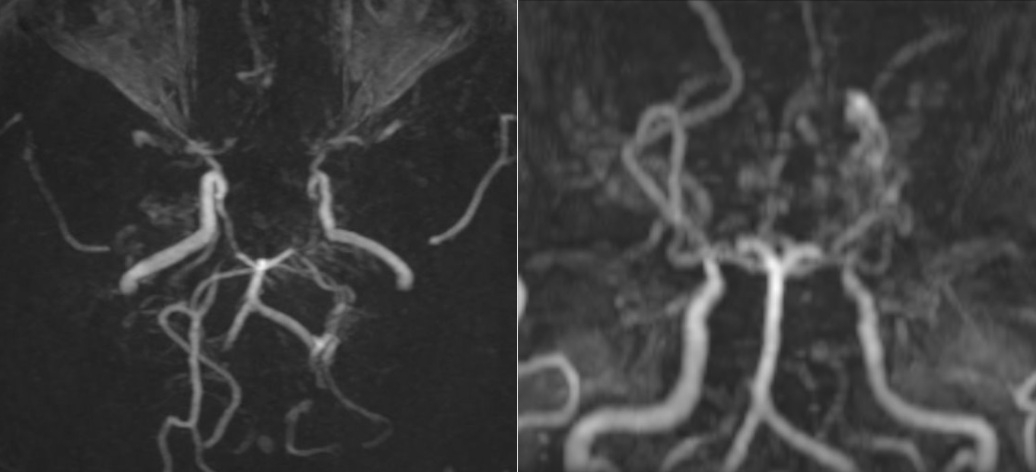

Các mạch máu não của bệnh nhân nhìn như “làn khói thuốc lá” trên phim chụp MRI.

Tại Bệnh viện đa khoa Medlatec, qua thăm khám lâm sàng, bệnh nhân không có dấu hiệu thần kinh khu trú hay tăng áp lực nội sọ. Để làm rõ nguyên nhân, bác sĩ chỉ định chụp cộng hưởng từ (MRI) sọ não. Kết quả MRI cho thấy, hình ảnh tổn thương hẹp tắc động mạch cảnh trong hai bên và các nhánh của đa giác Willis, xung quanh hình thành tuần hoàn bàng hệ với nhiều mạch máu nhỏ bất thường.

Đồng thời, trên chuỗi xung FLAIR, xuất hiện những dải tín hiệu sáng chạy dọc theo rãnh cuộn não, gợi hình ảnh “dây thường xuân” len lỏi trên bề mặt, phản ánh sự gia tăng tuần hoàn bàng hệ màng mềm để bù đắp cho tình trạng thiếu máu não do tắc nhánh mạch não. Bên cạnh đó, bác sĩ cũng phát hiện một hình ảnh tổn thương cũ ở vùng trán trái, là biến chứng của bệnh lý Moyamoya.

Theo BSCKI.BSNT Phạm Thị Yến, Chuyên khoa Chẩn đoán hình ảnh, Hệ thống Y tế Medlatec, trong chẩn đoán bệnh lý Moyamoya, chẩn đoán hình ảnh có vai trò rất quan trọng, giúp bác sĩ phân biệt với các bệnh lý gần tương tự như: xơ vữa động mạch, viêm màng não, chấn thương đầu…

Chẩn đoán hình ảnh phát hiện tình trạng hẹp hoặc tắc nghẽn phần cuối của động mạch cảnh trong sọ, rồi lan rộng ra các động mạch não trước, não giữa, não sau; phát hiện mạng lưới mạch máu bất thường ở vùng lân cận của các tổn thương dạng “làn khói thuốc”. Bệnh Moyamoya nếu không được phát hiện và điều trị kịp thời có thể dẫn đến đột quỵ, tàn phế hoặc tử vong.